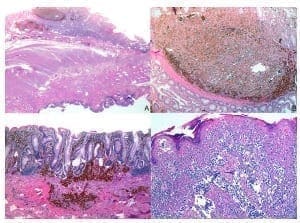

Con estos resultados, se decidió completar el trata­miento quirúrgico con intención curativa, procediéndose a una amputación abdómino-perineal, según la técnica descrita por Miles. El periodo posoperatorio nuevamente transcurrió sin complicaciones. El estudio anatomopato­lógico de la pieza de resección recto-sigmoidea confirmó la presencia de un melanoma nodular de localización perianal, con un espesor máximo de Breslow de 5 mm; asimismo, infiltración de la mucosa rectal, que alcanzaba 4 mm de profundidad. No hubo metástasis en los tres ganglios analizados. Los márgenes quirúrgicos estaban libres de neoplasia (figura 3).

Células pigmentadas atípicas con crecimiento intramucosoFigura 3. Estudio anatomopatológico. A. Agregado nodular de células pigmentadas atípicas con crecimiento intramucoso. Hema­toxilina y eosina, lupa. B. La misma imagen con mayor aumento. Hematoxilina y eosina, 10X. C. Melanoma que infiltra más allá de la muscularis mucosa, con patrón de pequeños nidos y células sueltas hiperpigmentadas, a distancia de la lesión nodular descrita, en otra zona de la mucosa del colon. Hematoxilina y eosina, 10 X. D. Crecimiento pagetoide de las células melánicas malignas en el epitelio escamoso anorrectal. Hematoxilina y eosina, 10X